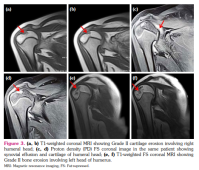

c) Cartilage lesion score: Nine (28.1%) joints in six patients showed cartilage lesions with a mean score of 0.3±0.6 (Figure 3a-d). Seven of these joints had Grade I and II joints had Grade II cartilage lesions (Figure 2a). The number of joints with cartilage lesions in sJIA and undifferentiated JIA were six (66.6%) and three (33.3%), respectively.

d) Bone erosion score: Bone erosions were seen in 15 (46.8%) joints in nine patients with a mean score of 0.6±0.8 (Figure 3e, f). Eleven joints had Grade I, three had Grade II, and one joint had Grade III bone erosion score (Figure 2a). The number of joints with bone erosions in sJIA, ERA, and undifferentiated JIA were 11 (73.3%), three (20%), and one (6.7%) joint, respectively.